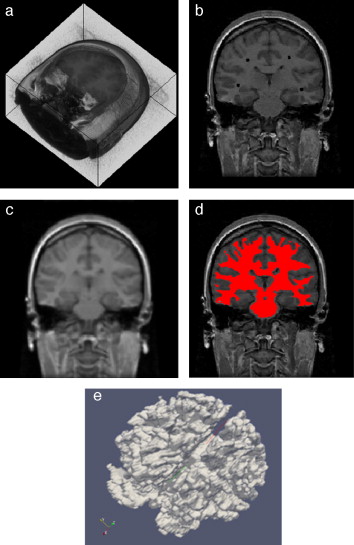

En la figura 10 se presenta el resultado de segmentar la materia blanca del cerebro en IRM empleando la rutina de Region Growing mencionada. En la figura 10 .a se observa la vista 3D del volumen inicial. En la figura 10 .b se observa uno de los cortes de la figura 10 .a con la selección de cuatro semillas iniciales de forma esférica dentro de la zona de la materia blanca. En la figura 10 .c se observa en color rojo la zona región de la materia blanca obtenida al finalizar la rutina de segmentación. En la figura 10 .d se presenta una vista 3D de la zona de la materia blanca segmentada.

Segmentación de materia blanca empleando Region Growing en IRM del cerebro. (a) ...

Figura 10.

Segmentación de materia blanca empleando Region Growing en IRM del cerebro. (a) Volumen formado por varios cortes de IRM cerebral original. (b) Vista de un corte coronal con la lección de cuatro semillas iniciales. (c) Vista del corte coronal (b) con la materia blanca segmentada con Region Growing . (d). Vista volumétrica de la materia blanca segmentada en (c).

En la figura 26 son presentados las vistas tridimensional del volumen de la zona de la materia blanca proporcionado por BrainWeb, el volumen obtenido con Region Growing y volumen obtenido con Watershed.

Vista volumétrica de la zona de la materia blanca. (a) Volumen original de la ...

Figura 26.

Vista volumétrica de la zona de la materia blanca. (a) Volumen original de la materia blanca proporcionado por BrainWeb. (b) Vista 3D del volumen obtenido con Region Growing en la figura 26 .d. (c) Vista 3D del volumen obtenido con Watershed en la figura 27 .b.